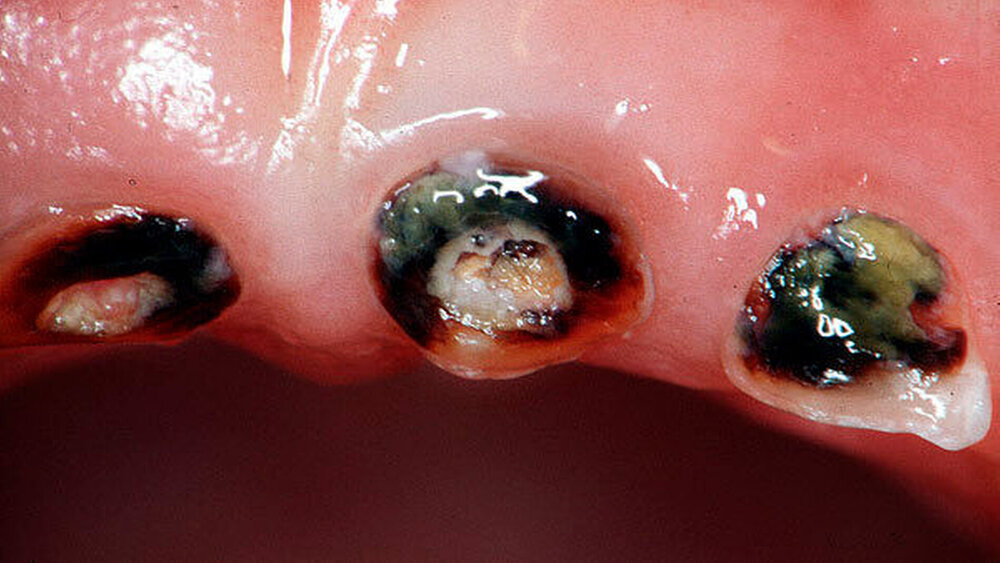

Allen Studien gemein war ein hohes Verzerrungsrisiko, in manchen Studien waren die Stichprobengrößen zu klein, um genaue Ergebnisse zu liefern. Unterschiedliche Anwendungsintervalle beziehungsweise die Häufigkeit der Anwendung konnten nicht abschließend bewertet werden, weil in allen Studien eine sehr geringe Beweissicherheit vorlag. Über Verfärbungen als unerwünschte Wirkung lagen nur sehr wenige Berichte vor.